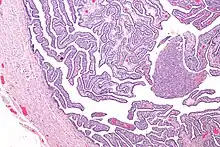

Definitive criteria include histopathologic evidence of endometritis, thickened filled fallopian tubes, or laparoscopic findings. Gram stain/smear becomes definitive in the identification of rare, atypical and possibly more serious organisms.[24] Two thirds of patients with laparoscopic evidence of previous PID were not aware they had PID, but even asymptomatic PID can cause serious harm.